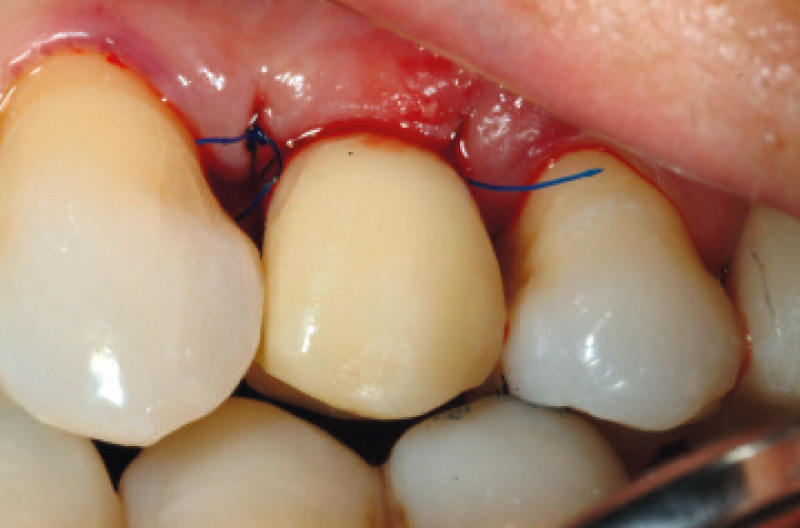

Il secondo fattore chiave per il mantenimento dell’estetica nel tempo è il SIGILLO MICROBIOLOGICO della connessione impianto-moncone. Grazie alla connessione a cono Morse Leone, i tessuti perimplantari vengono disturbati meno, rendendo possibili eccellenti guarigioni e il mantenimento dei tessuti duri e molli negli anni (Figg. 3 – 5).

Figg. 3, 4 – Eccellente guarigione dei tessuti molli alla rimozione dei tappi di guarigione

Fig. 4